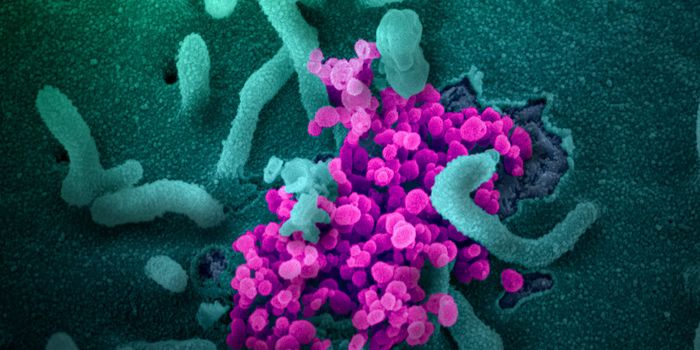

OCT 22, 2021Genetics & GenomicsTo clear a viral infection, the human body has to mount an effective immune response. After detecting the pathogen, immu ...